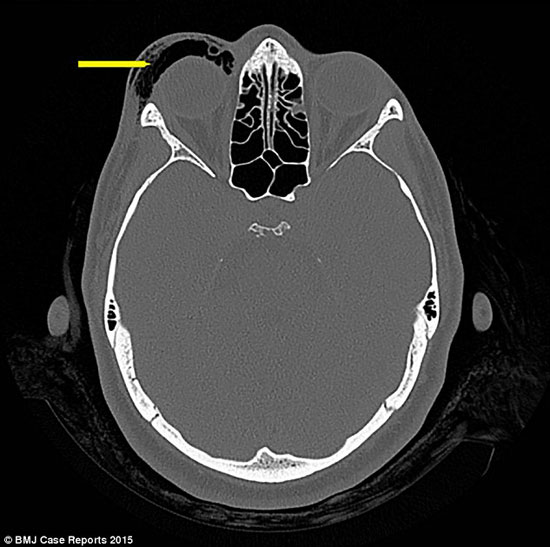

وأوضحت التقارير، أن الفحص الشامل أظهر أن سبب تورم وانتفاخ العين، بذلك الحجم، جاء نتيجة تجمع الهواء في الأنسجة الرخوة حول العينين، وذلك جراء إغلاق الفم والأنف، لكتم النفس في أحد تمارين النفس المعروفة.

تعرضت سيدة تبلغ من العمر 32 عامًا، لانتفاخ شديد في العين؛ جراء ممارسة تمارين حبس الأنفاس لفترات طويلة، ولم يجد الأطباء طرقًا لعلاج الانتفاخ، مما يهددها بفقدان البصر.